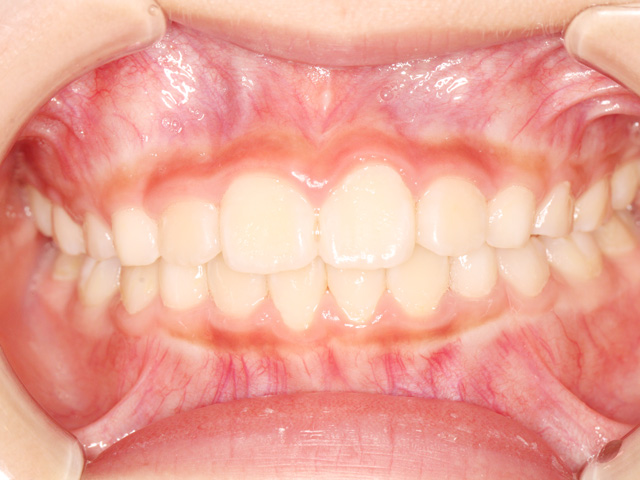

笑ったときに前歯が出ている、噛み合わせがズレている、歯が重なって生えてきている…。実はこれらは、成長とともに自然に治ることもあれば、逆に悪化してしまうケースもあります。

小児矯正は、単に歯をきれいに並べる治療ではありません。顎の成長をコントロールし、将来の歯並びや噛み合わせを根本から整えることを目的としています。これは成長期にしかできない、いわば「未来への投資」のようなものです。

歯並びを改善させるだけでなく、それと同時に生え変わっていない永久歯が、将来並ぶスペースを確保したり、上下の顎のバランスを整えたりします。

例えば、顎が小さいと、永久歯が生えるスペースが足りず、歯が重なったり、外に押し出されたりします。これを無理に並べようとすると、大人の矯正では抜歯が必要になることもあります。しかし、成長期に顎の幅を広げておけば、そもそも抜歯をしなくても済む可能性が高くなるのです。小児矯正では、装置を使って顎の成長方向を誘導したり、舌や唇の使い方、呼吸の仕方といった口周りの癖を改善することもあります。これらは歯並びに大きな影響を与える要素であり、見過ごされがちですが非常に重要です。

小児矯正と大人の矯正の最大の違いは、成長を利用できるかどうかです。この貴重なタイミングを活かすことで、より自然で安定した歯並びを目指すことができます。